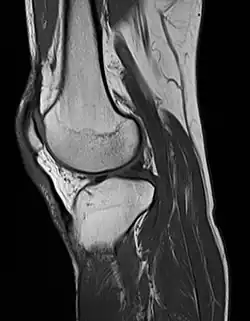

MRI of the knee

MRI uses strong magnetic fields to align atomic nuclei (usually hydrogen protons) within body tissues, then uses a radio signal to disturb the axis of rotation of these nuclei and observes the radio frequency signal generated as the nuclei return to their baseline states.[15] The radio signals are collected by small antennae, called coils, placed near the area of interest. An advantage of MRI is its ability to produce images in axial, coronal, sagittal and multiple oblique planes with equal ease. MRI scans give the best soft tissue contrast of all the imaging modalities. With advances in scanning speed and spatial resolution, and improvements in computer 3D algorithms and hardware, MRI has become an important tool in musculoskeletal radiology and neuroradiology.

One disadvantage is the patient has to hold still for long periods of time in a noisy, cramped space while the imaging is performed. Claustrophobia (fear of closed spaces) severe enough to terminate the MRI exam is reported in up to 5% of patients. Recent improvements in magnet design including stronger magnetic fields (3 teslas), shortening exam times, wider, shorter magnet bores and more open magnet designs, have brought some relief for claustrophobic patients. However, for magnets with equivalent field strengths, there is often a trade-off between image quality and open design. MRI has great benefit in imaging the brain, spine, and musculoskeletal system. The use of MRI is currently contraindicated for patients with pacemakers, cochlear implants, some indwelling medication pumps, certain types of cerebral aneurysm clips, metal fragments in the eyes, some metallic hardware due to the powerful magnetic fields, and strong fluctuating radio signals to which the body is exposed. Areas of potential advancement include functional imaging, cardiovascular MRI, and MRI-guided therapy.